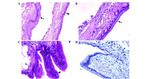

MUC1 Antibody in Immunohistochemistry (Paraffin) (IHC (P))

MUC1 Antibody in Immunohistochemistry (IHC)